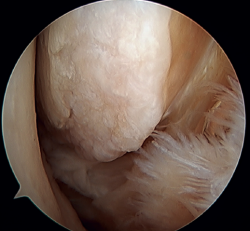

A recent consensus(64) recommends reconstruction of the ATFL and CFL (Figures 5 and 6) in cases of generalized laxity or when there is poor tissue quality. Other indications would be when there are doubts about subtalar stability or in patients with a ruptured CFL. For some authors, BMI > 30 kg/m2 would also be an indication for this technique.

Figure 5. Tearing of the anterior talofibular ligament and calcaneofibular ligament with poor tissue quality of the ligament remnant.